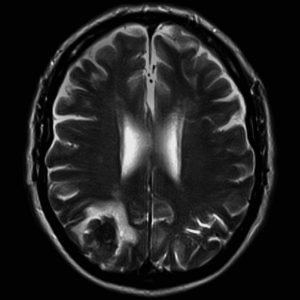

Ressonância Magnética De Alto Campo

É o método de diagnóstico por imagem mais moderno disponível no mercado, capaz de obter imagens de várias regiões do corpo com altíssima definição e resolução. É um exame inócuo, pois as imagens são obtidas através de campo magnético e pulsos de radiofrequência, não sendo necessária exposição a radiação ionizante.